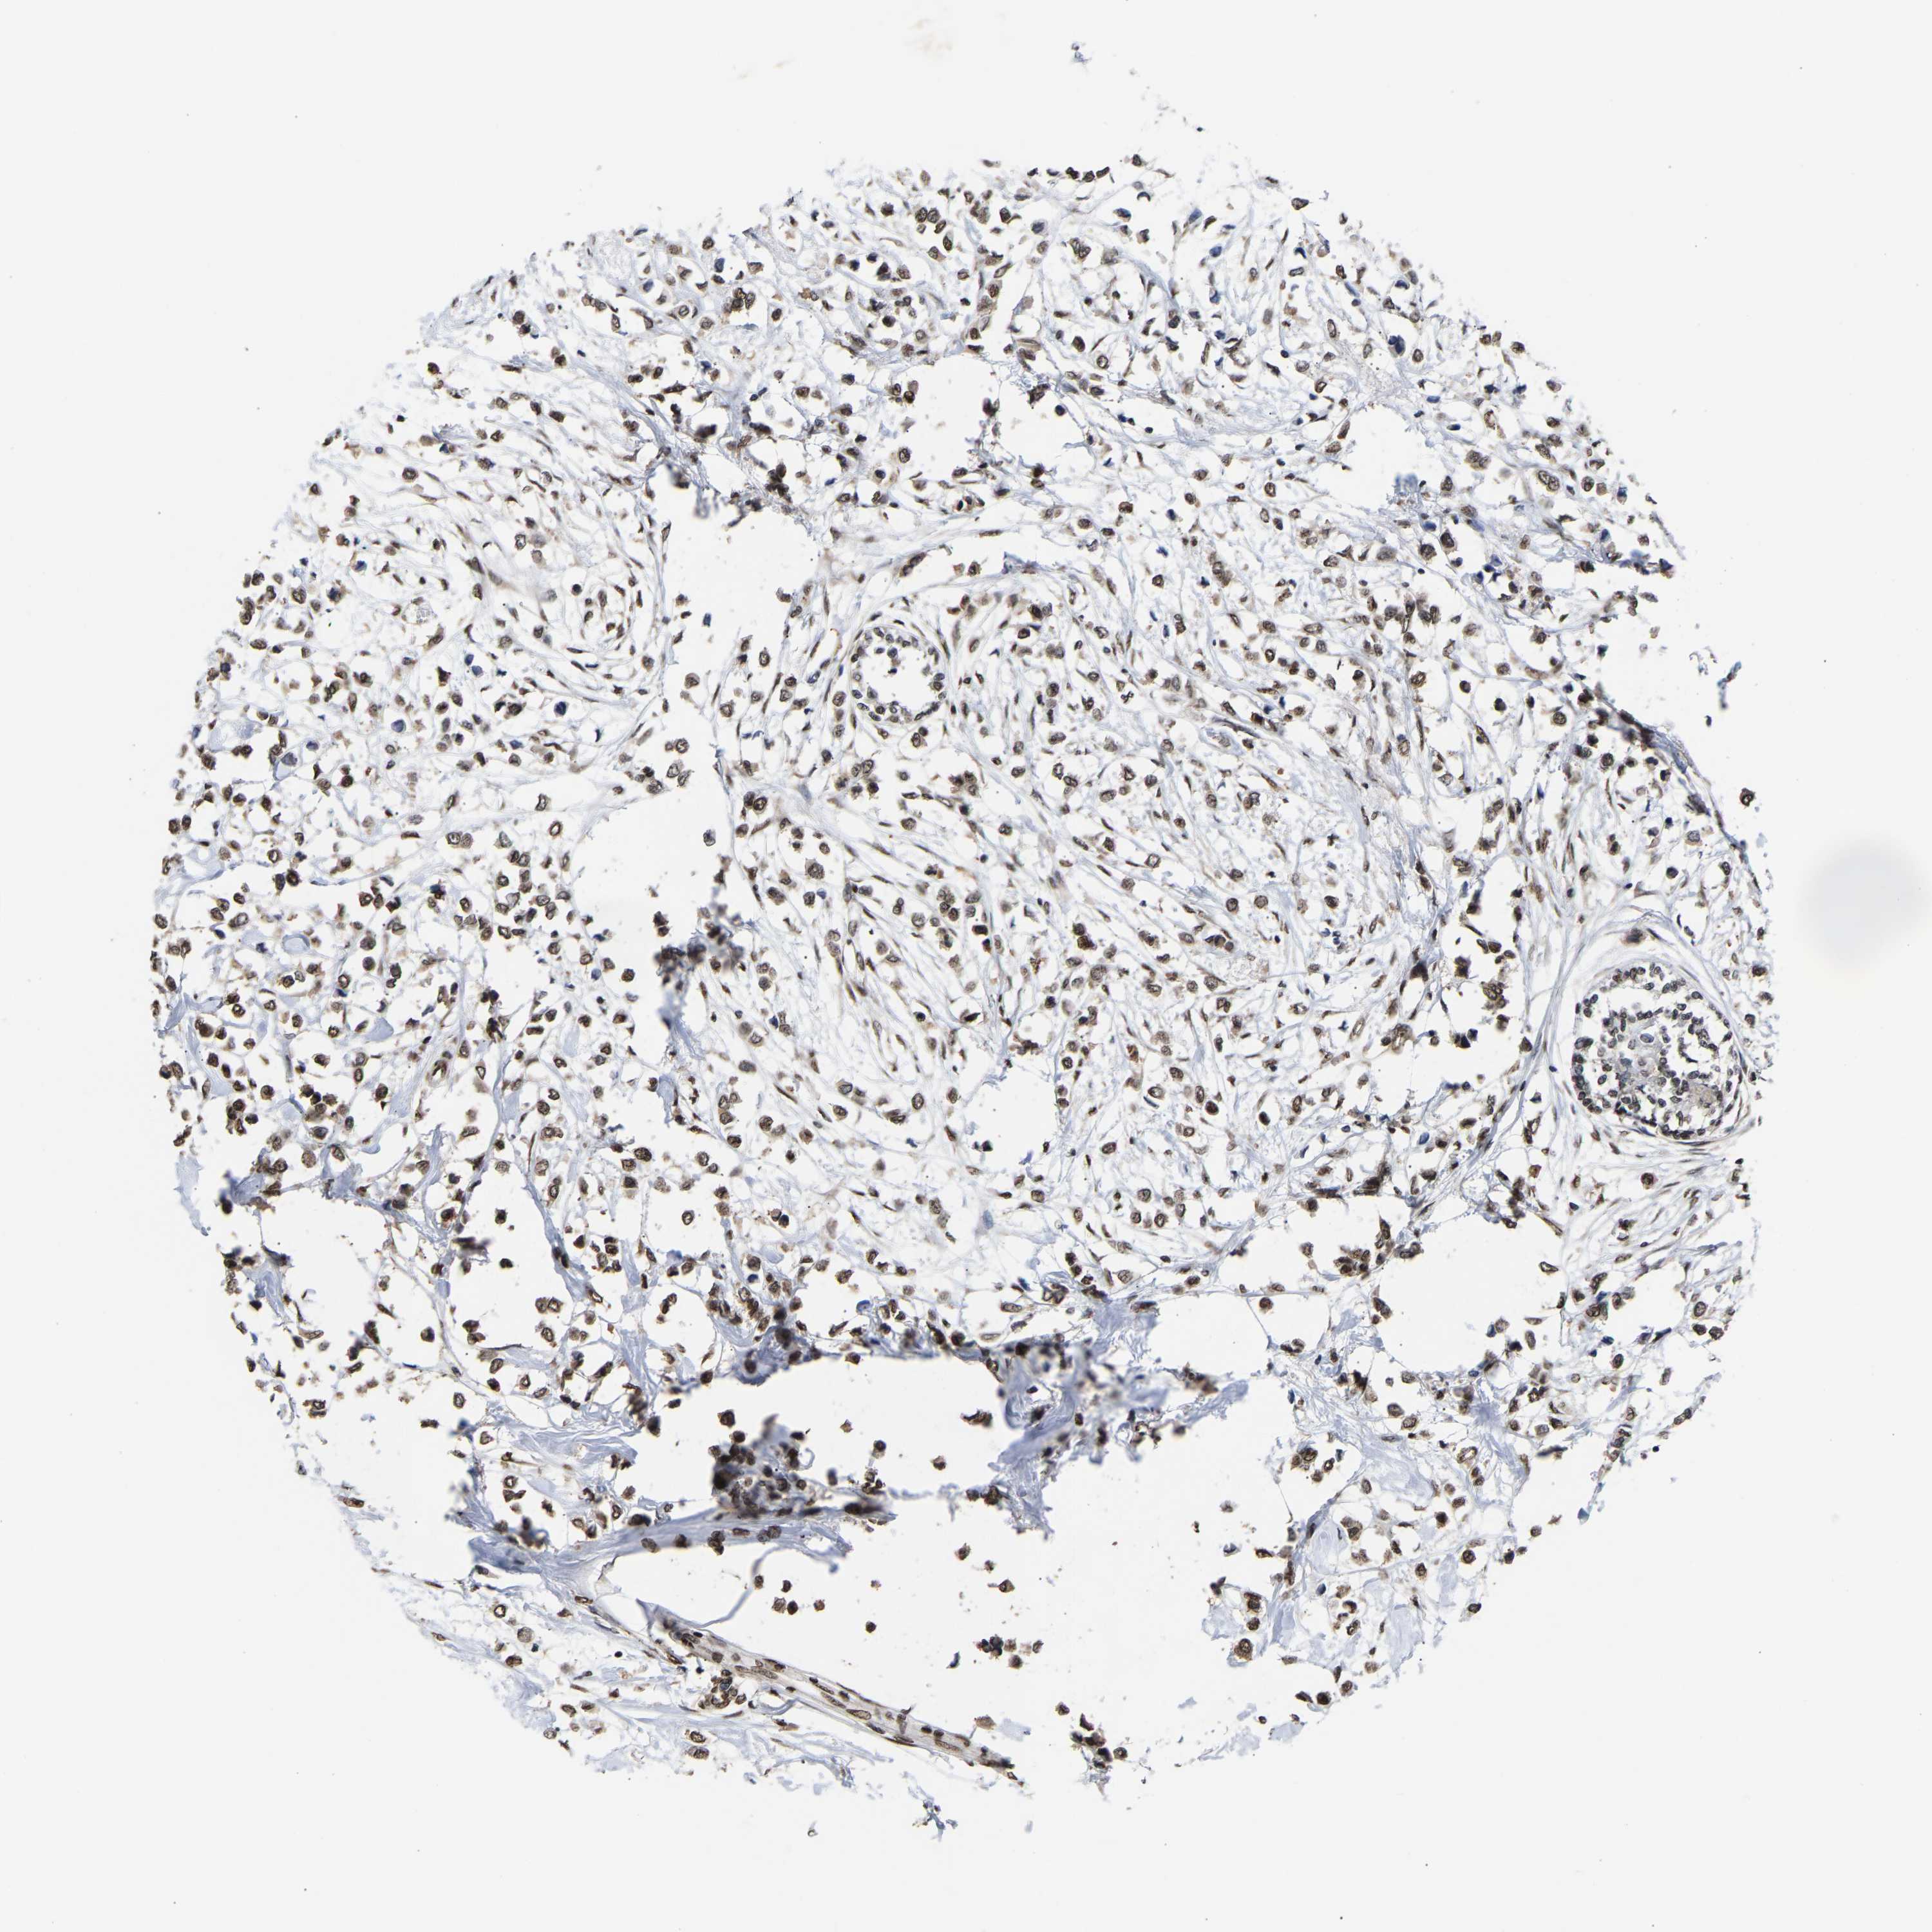

CANCER BREAST CANCER Show tissue menu

BRCA TCGA BRCA VALIDATION PROTEIN EXPRESSION